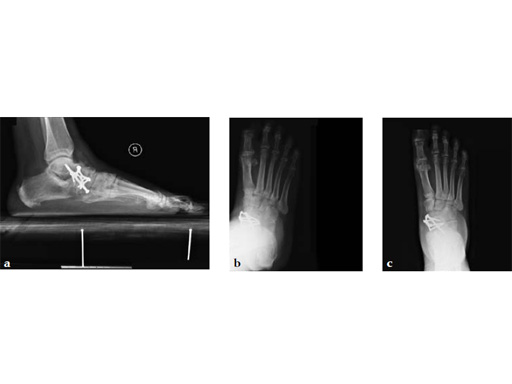

Case 5: First TMT, straight fusion and TMT fusion plates

A 46-year-old obese woman with coronary artery disease had sustained a Lisfranc injury while performing an exercise program. She was unable to weight bear and used an electric scooter.

In an effort to restore her ability to exercise and taking into consideration her body weight and upper extremity weakness, a decision was made to use the variable angle locking compression plate. These postoperative x-rays were obtained at 3 months, one month after beginning weight bearing. The patients pain was reduced and she was able to resume a progressive exercise program after 4 months following surgery.

Case provided by Michael Castro, Scottsdale, Arizona